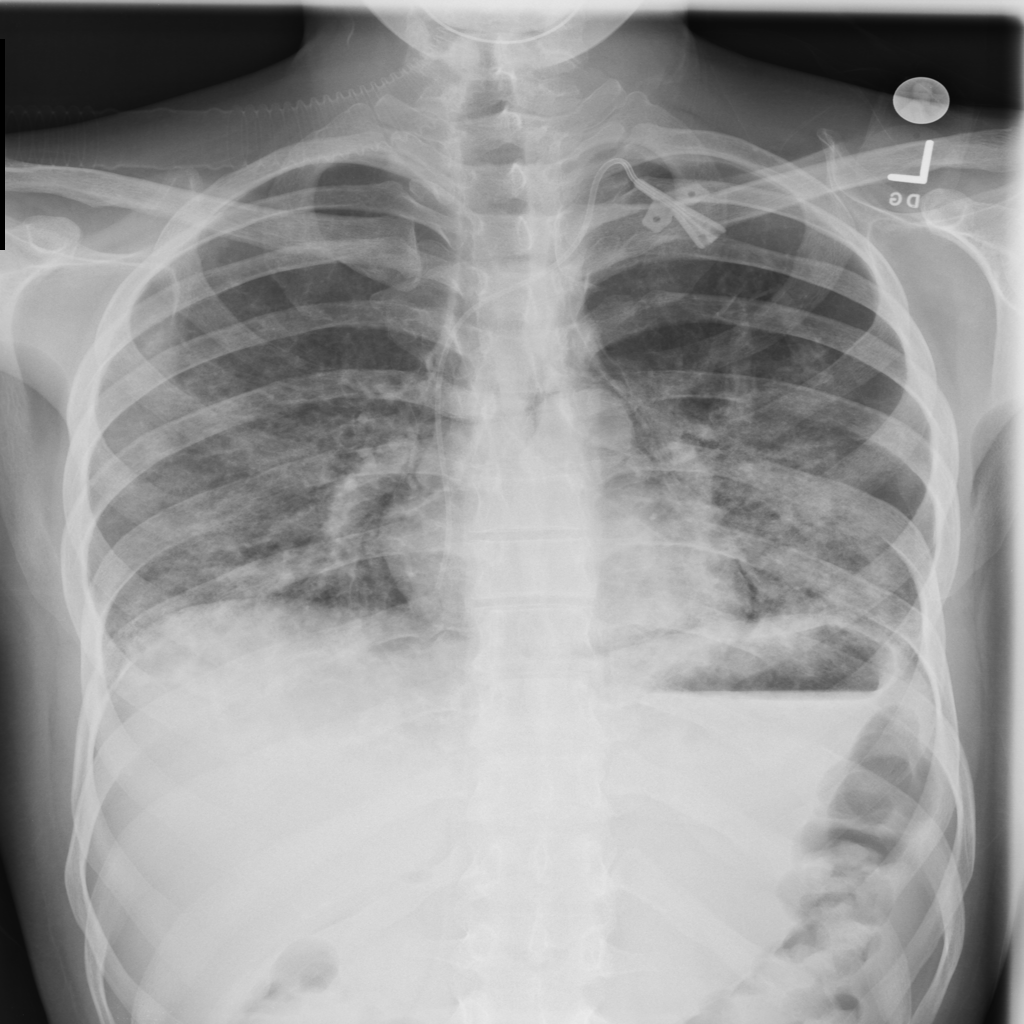

PAT-C1A7 · IMG-004Consolidation

PAT-C1A7 · IMG-004

PA